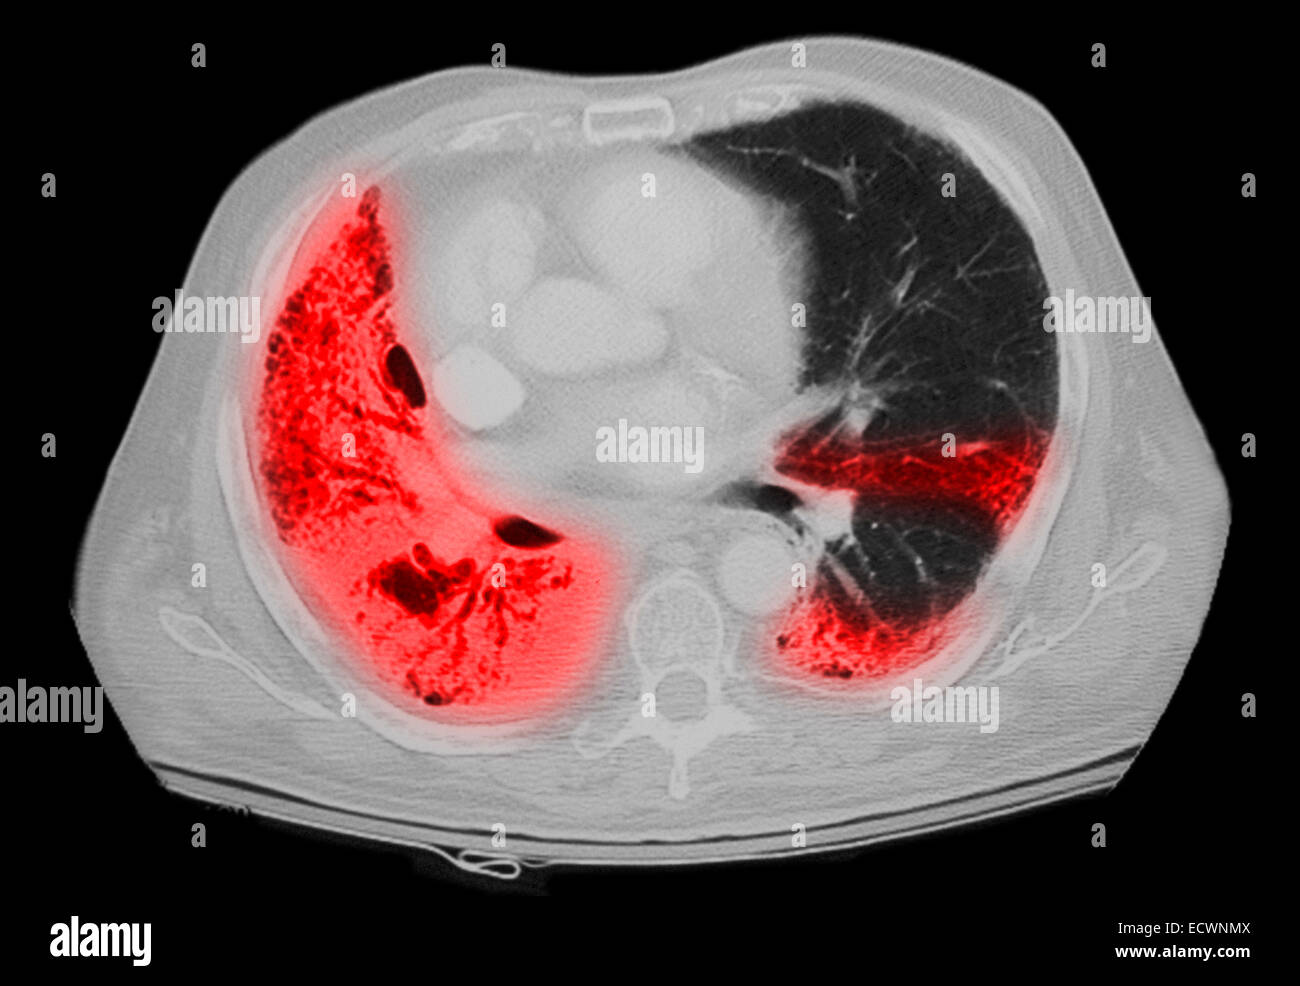

From www.alamy.com

CT scan of the chest showing pneumonia Stock Photo Alamy Will A Chest Ct Show Pneumonia Bacterial lobar pneumonia or left ventricular failure), the patient will be. A ct scan of the chest may be done to see finer details within the lungs and detect pneumonia that may be more difficult to. Sometimes further imaging with ct is needed if there is high. But in most cases, you can’t tell simply from the ct scan. When. Will A Chest Ct Show Pneumonia.